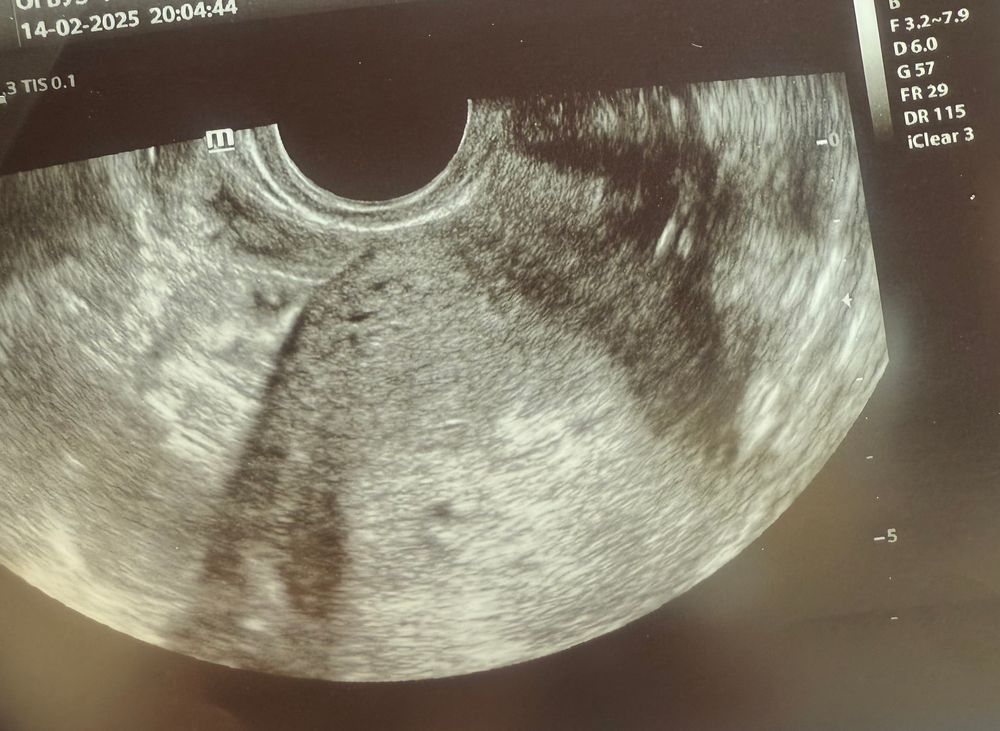

Нашли ПЯ в матке 😳

плодное яйцо 9 мм и ХГЧ ниже 1000 возможно только в ситуации : 1) он был ранее выше и уже упал 2) косяк лаборатории и неправильное определение ну и 3) это не плодное яйцо.

Поля, по узи ПЯ на 4 недели, по месячным 6. Овуляцию не отслеживала, возможно была поздняя.